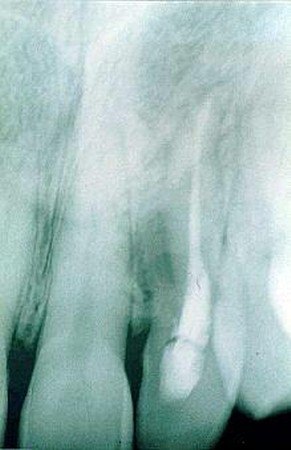

Orthopanthomografické (OPG) a intarorálne RTG snímkovanie je nevyhnutné pre stanovenie presnej diagnózy a plánu ošetrenia, pri preventívnych prehliadkach, ale aj pri bežnom ošetrení. Zobrazí už počiatočné kazy na miestach, ktoré nie sú na prvý pohľad viditeľné. Rovnako je dôležité aj pri endodoncii, teda pri ošetrení koreňových kanálikov, pri zápaloch nervu, pri paradentóze a kývavosti zubov, prípadne posúdení nutnosti extrakcie zuba.

V našej praxi sa pri diagnostike ochorení v dentoalveolárnej oblasti používa zobrazovacia technika, ktorá je neoddeliteľnou súčasťou vyšetrenia pacienta, ako aj následných ošetrení. Zhotovujeme digitálne intraorálne snímky. Ich výhodou je okamžité zobrazenie na monitore počítača, niekoľkonásobne znížená doba expozície, možnosť uloženia záznamu pre porovnanie do budúcnosti, možnosť aktívnej práce so snímkami, zobrazenie detailov, zmena kontrastu, farebné zobrazenie. Tieto snímky majú výrazný informatívny význam pri diagnostike tvrdých tkanív (zuby, kosti), závesný aparát zubov, pre plánovanie protetických prác, celkových sanácií, ale predovšetkým pri plánovaní implantačnej terapie.